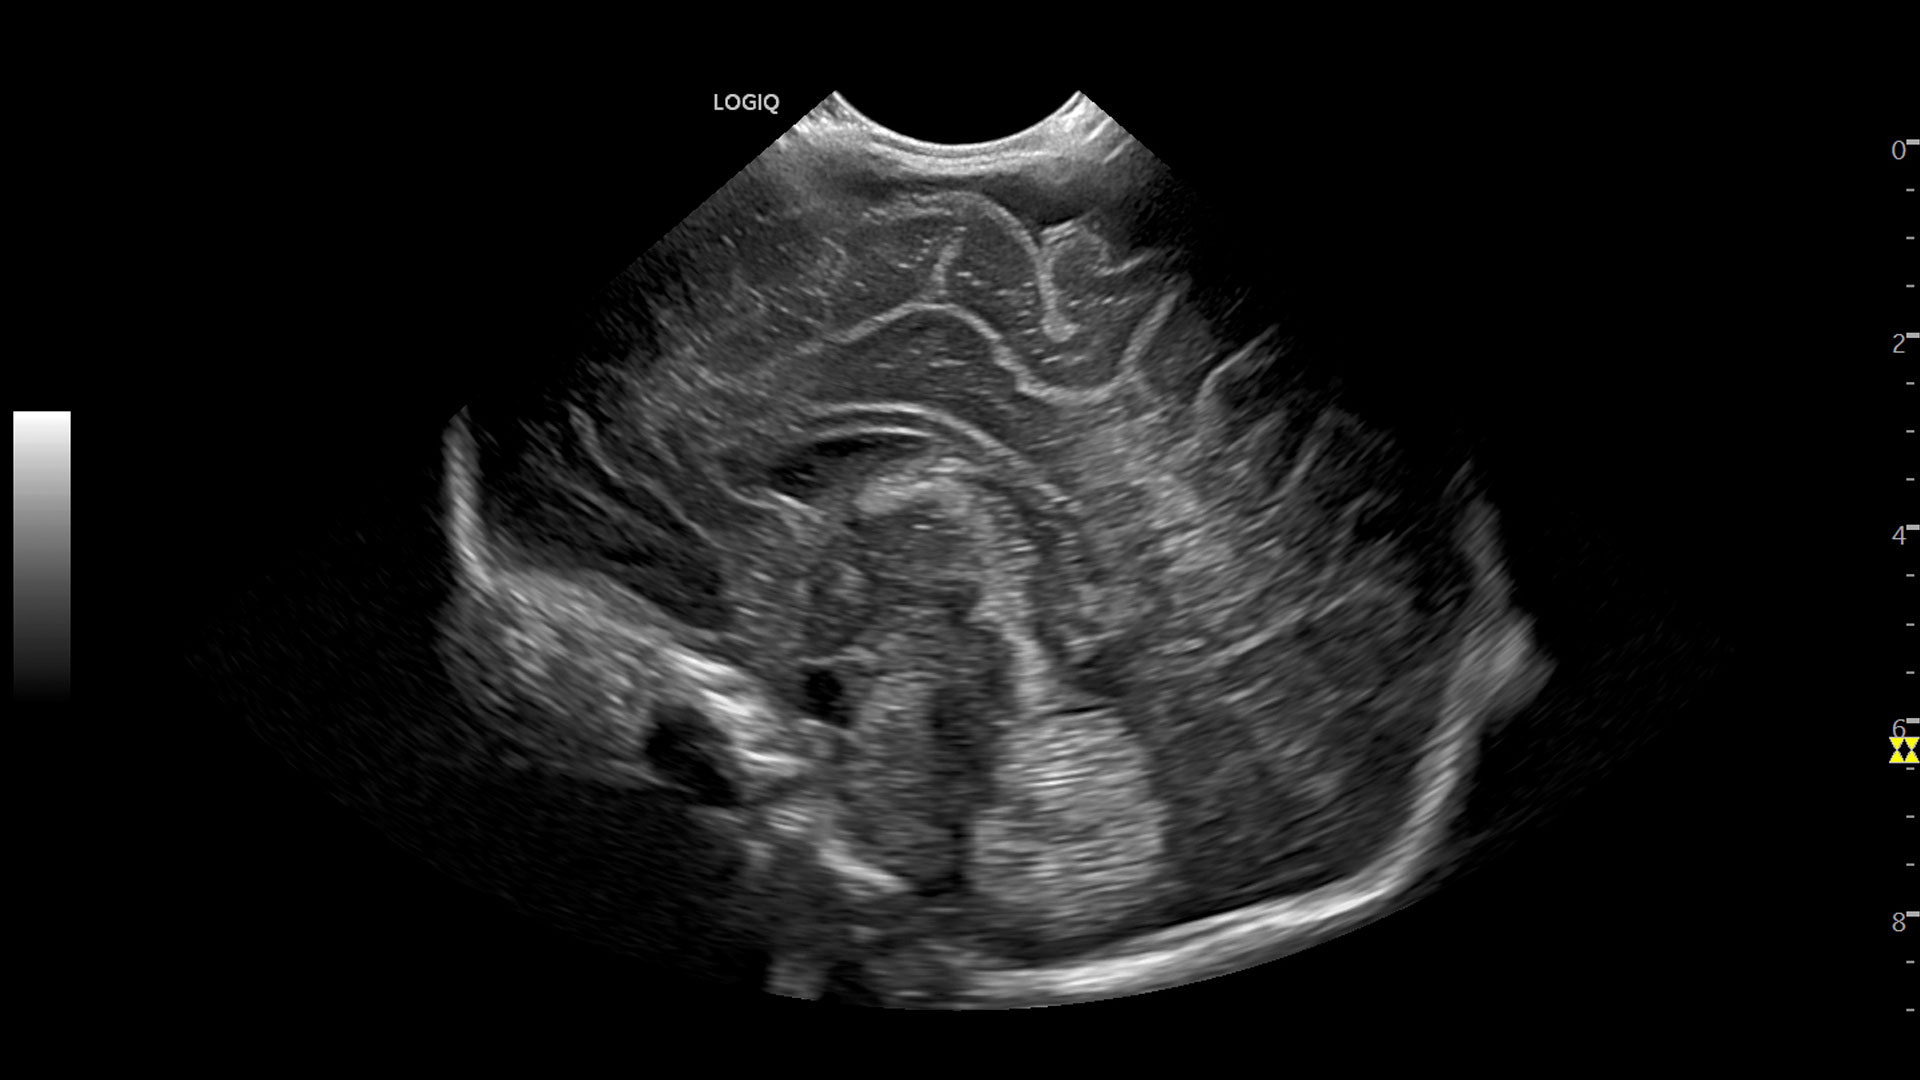

Multi-purpose capabilities, including liver, cardiac, OB/GYN, vascular, breast, thyroid, musculoskeletal, urologic, and pediatric studies.

Superb image quality with XDclear probes: Powerful high fidelity and broad bandwidth produce high resolution images whether scanning superficial or deep targets.

Advanced imaging and visualization tools, including:

• 3D/4D with SonoRenderlive